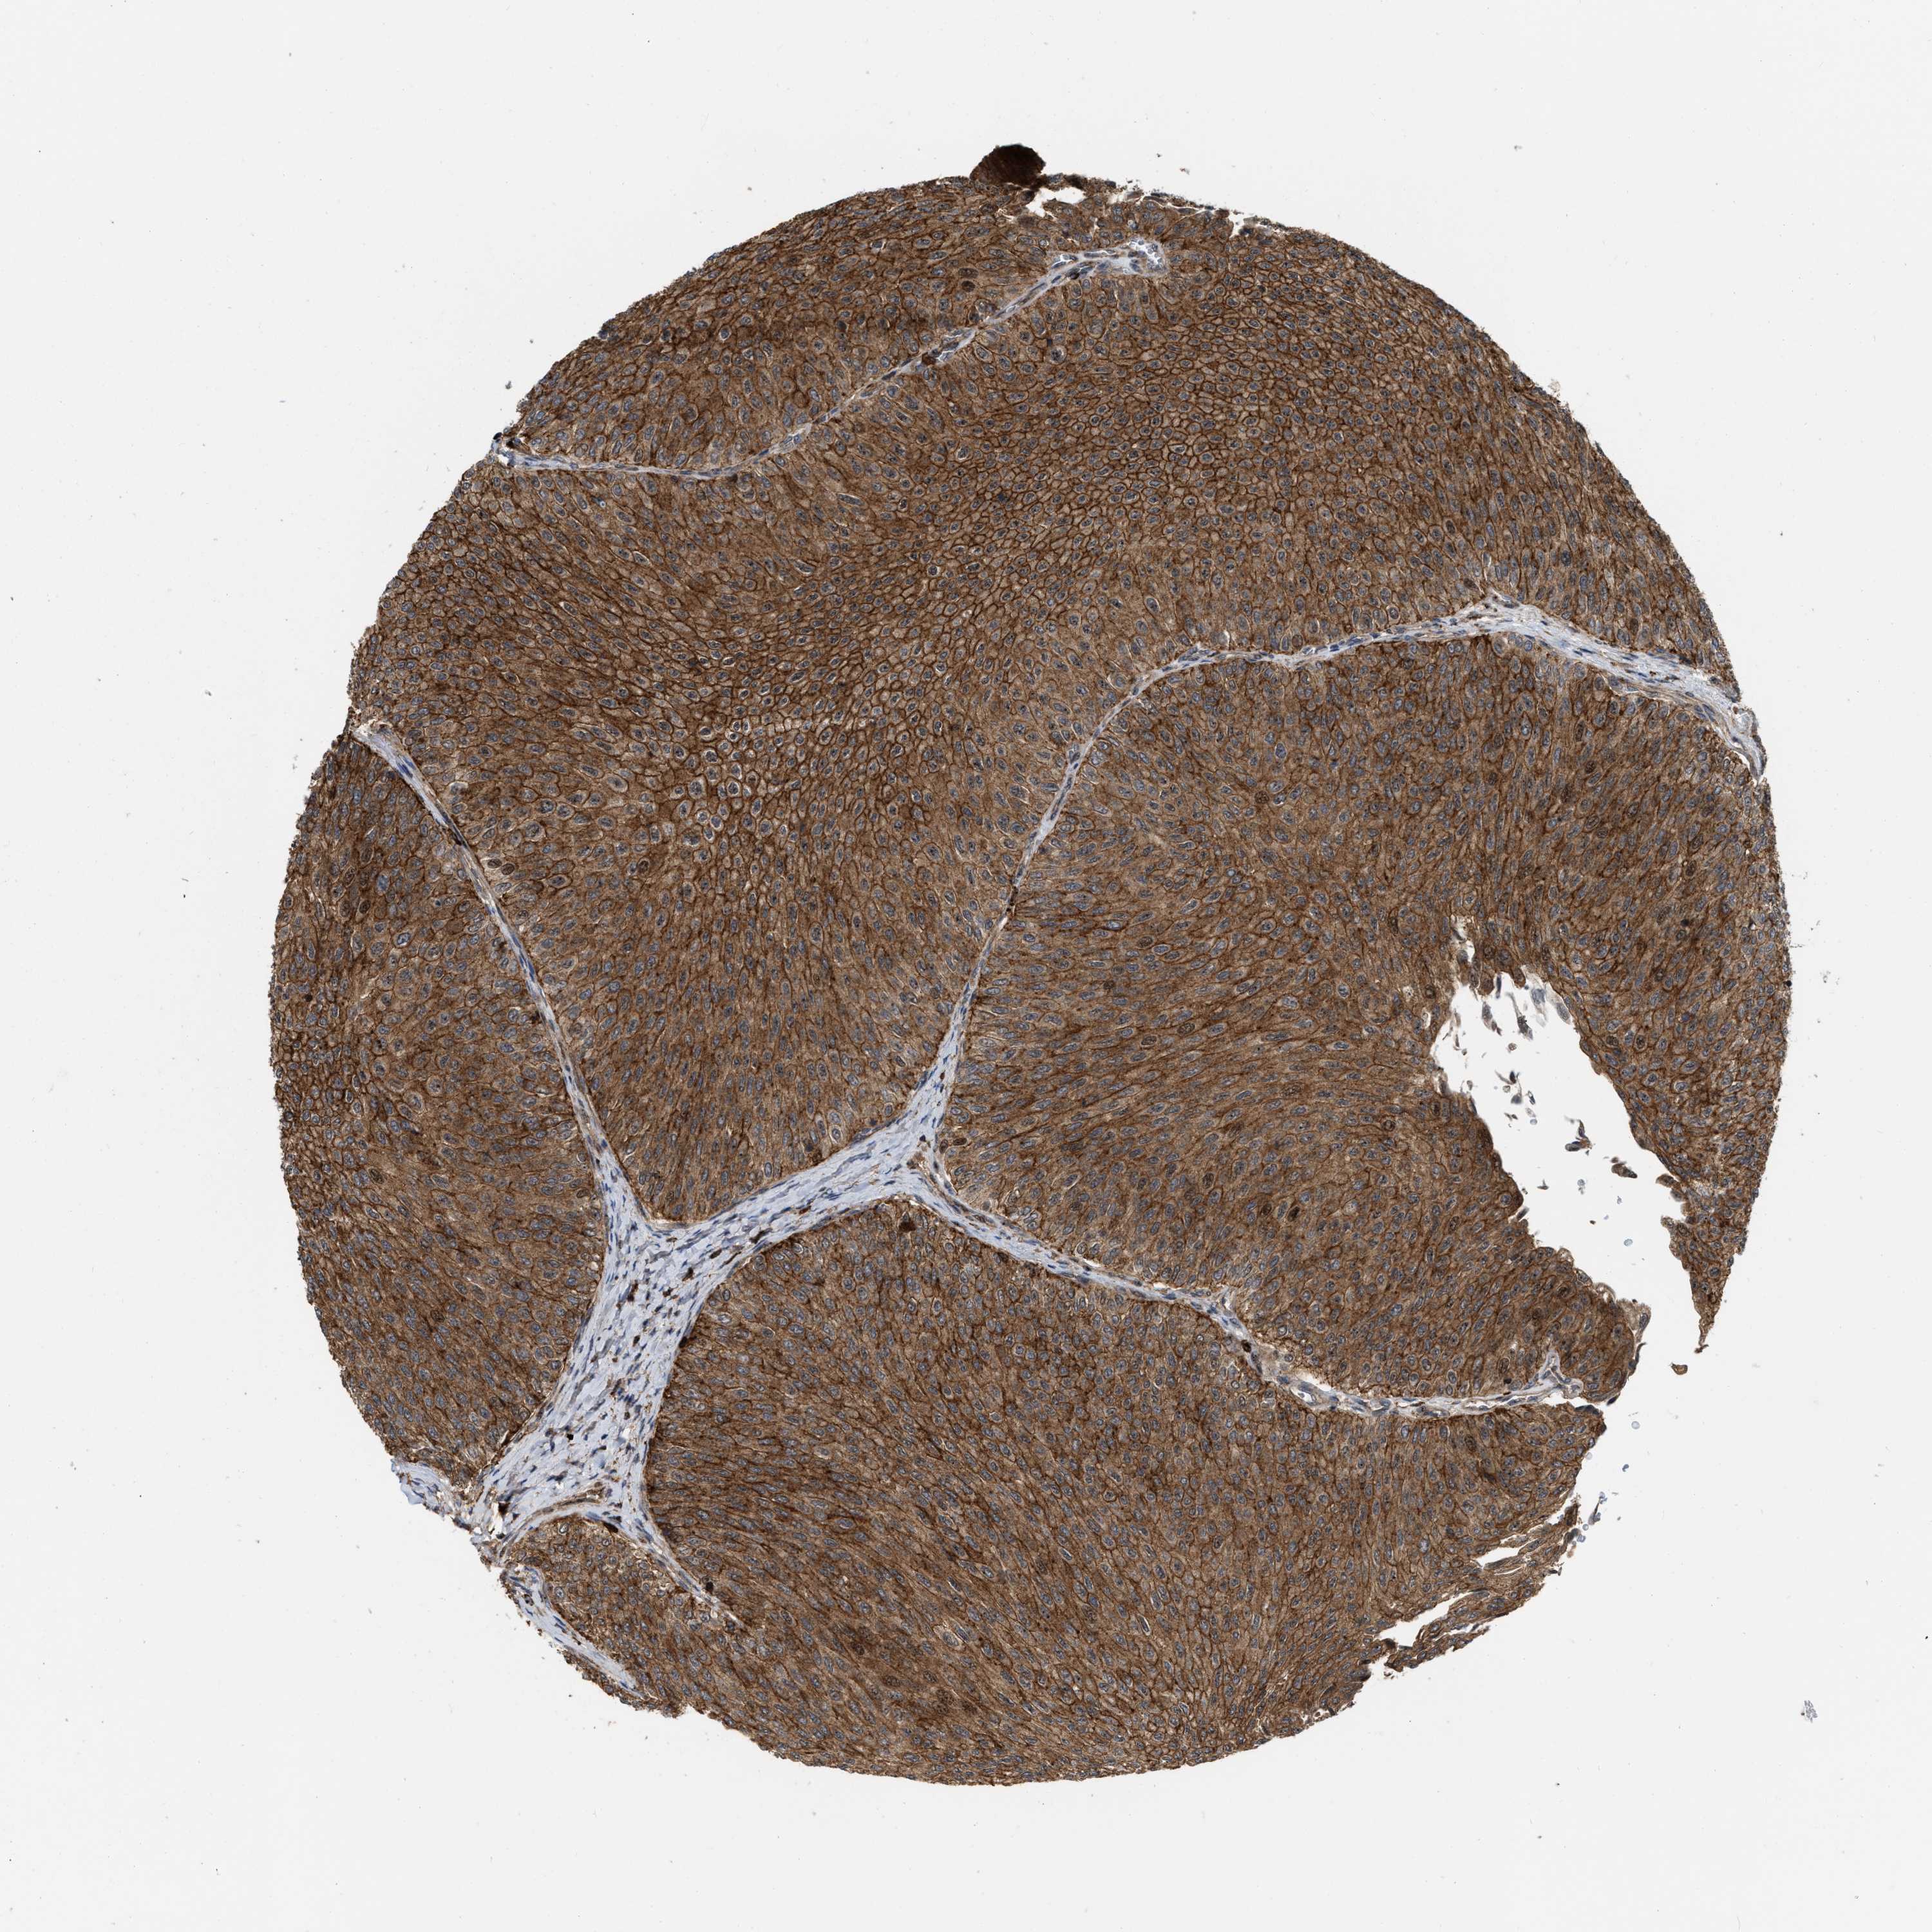

UROTHELIAL CANCER - Protein expressioni

A mouse-over function shows sample information and annotation data. Click on an image to view it in a full screen mode. Samples can be filtered based on level of antibody staining by selecting one or several of the following categories: high, medium, low and not detected. The assay and annotation is described here.

Note that samples used for immunohistochemistry by the Human Protein Atlas do not correspond to samples in the TCGA dataset.

Antibody stainingi

Antibody staining in the annotated cell types in the current human tissue is reported as not detected, low, medium, or high, based on conventional immunohistochemistry profiling in selected tissues. This score is based on the combination of the staining intensity and fraction of stained cells.

Each image is clickable and will lead to virtual microscopy that enables deeper exploration of all samples and also displays staining intensity scores, fraction scores and subcellular localization as well as patient and tissue information for each sample.

Antibody HPA019515

Staining

High

Medium

Low

Not detected

Intensity

Strong

Moderate

Weak

Negative

Quantity

>75%

75%-25%

<25%

None

Location

Urothelial carcinoma, Low grade

Urothelial carcinoma, High grade